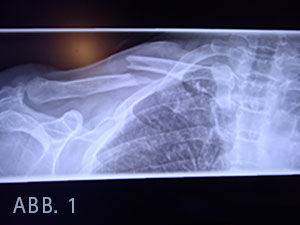

Bei Kennzeichnung der kompletten Frakturlinie zeigte sich, dass das relativ spitz zulaufende Klavikulabruchstück (Abb. 1) im Bereich der Gefäß- Nervenstraße lag, wodurch eine Arrodierung bei Sturz oder bei Schulterbewegungen vor der Ruhigstellung nicht ausgeschlossen werden kann, im Sinne eines zeitverzögerten Auftretens eines Pseudoaneurysmas der Arteria subclavia.

Die vierte Schraube in der LC - Platte (Locking Compression Plate) von medial perforiert die Gegenkortikalis deutlich (Abb. 2) und liegt 5,25 cm vom Akromioklavikulagelenk (AC) und 8,25 cm vom Sternoklavikulagelenk (SC) entfernt.